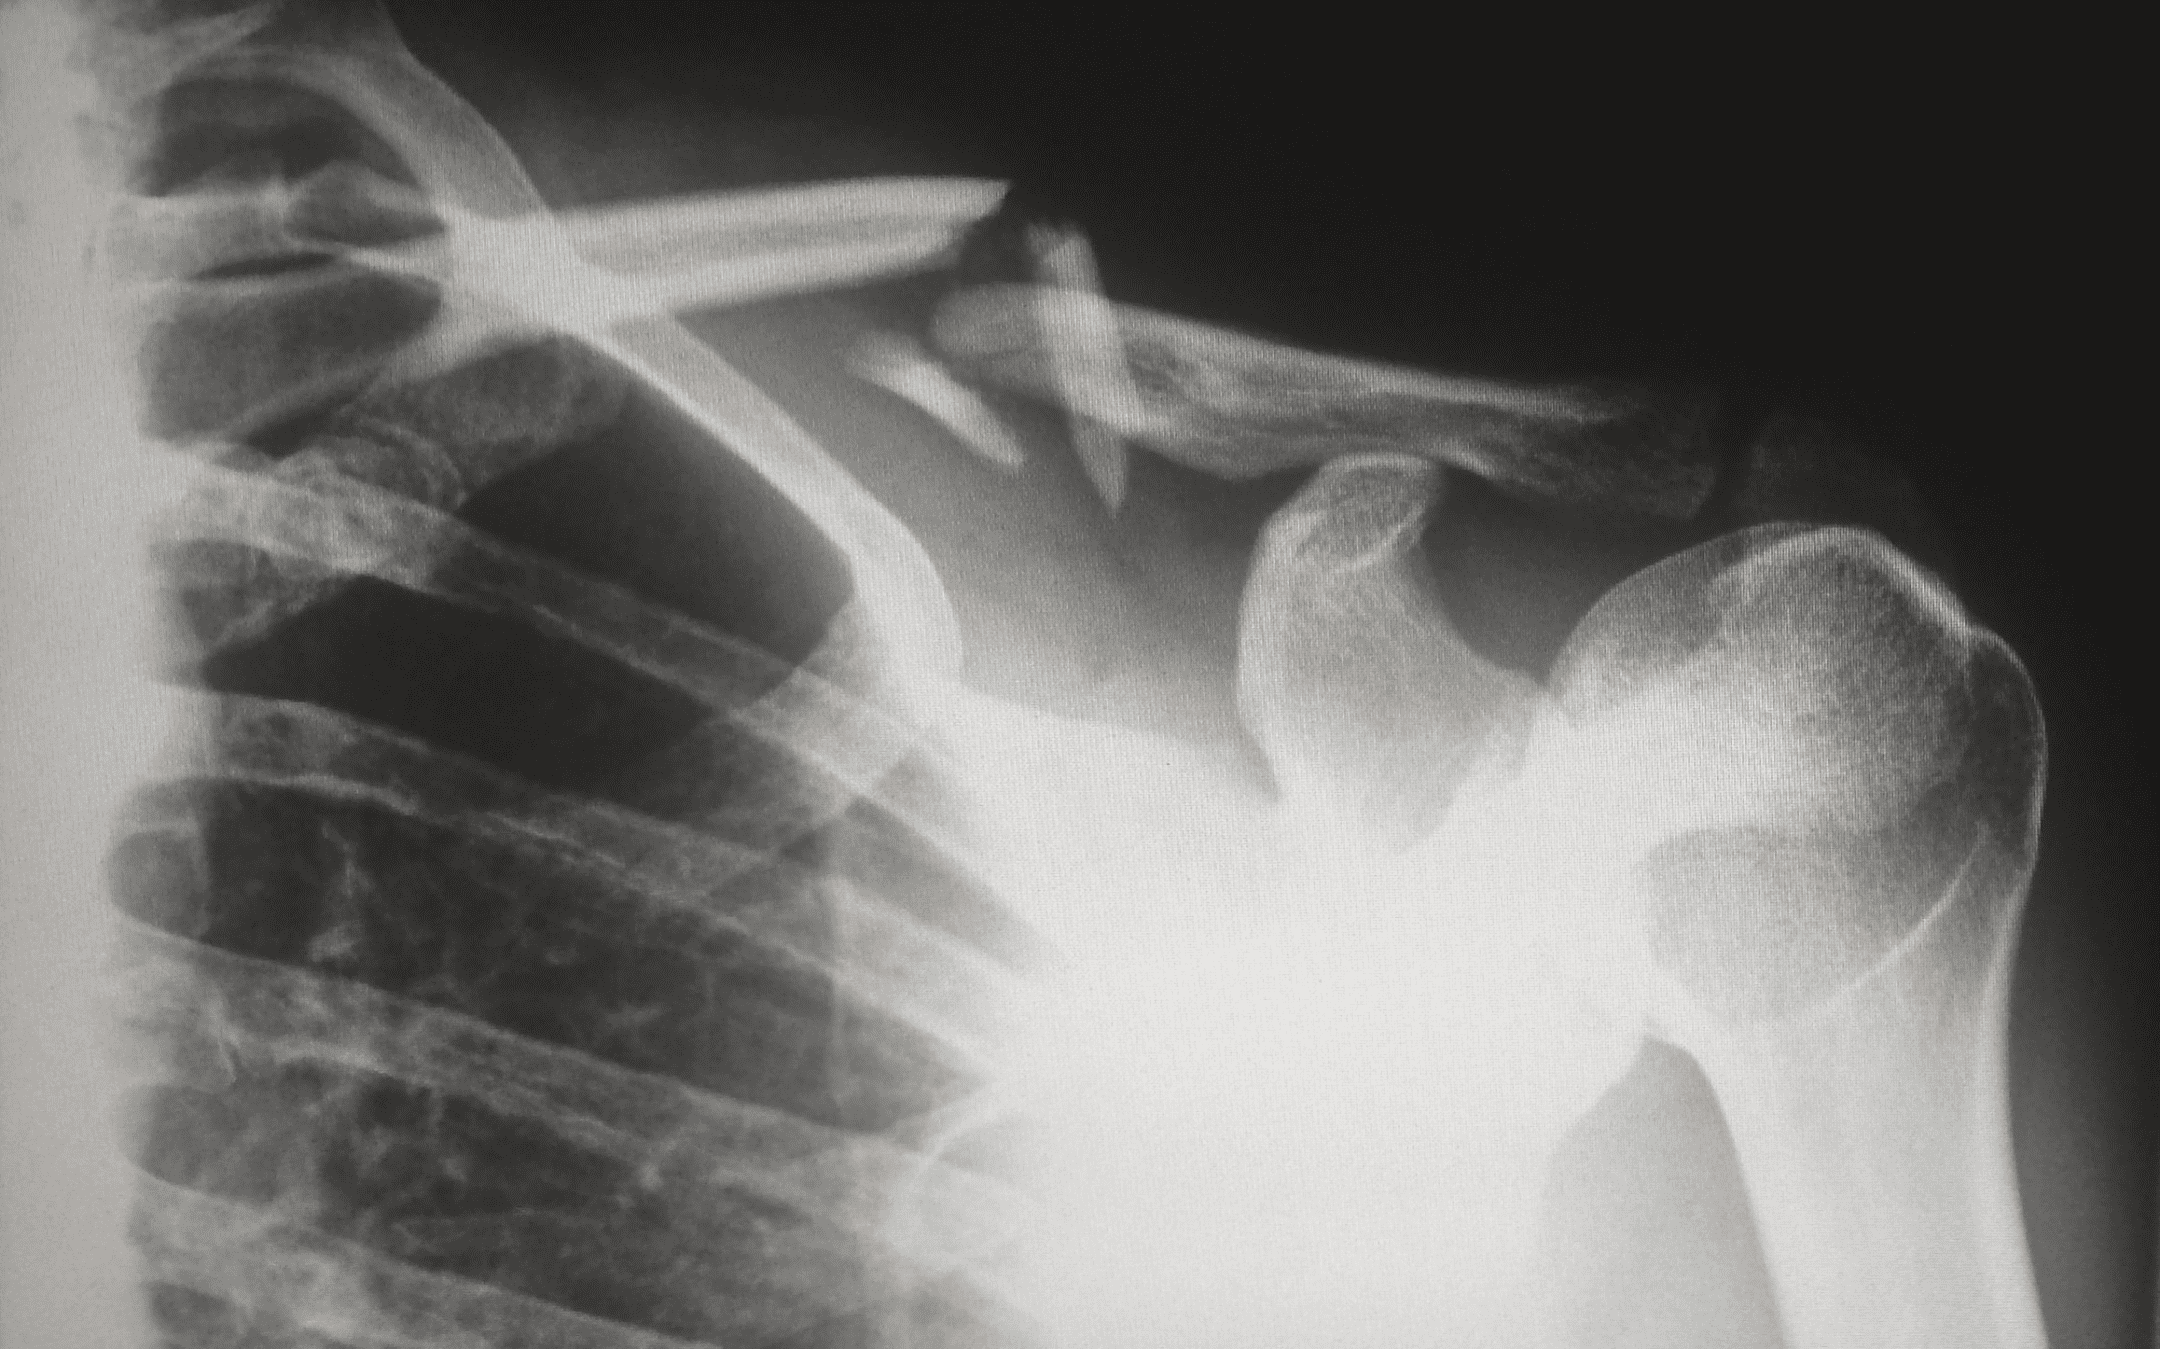

The shoulder joint requires some of the strongest muscles in the body to attach to the bone of the arm via very small attachment sites.

Image: RSatUSZ / CC BY SA - Creative Commons Attribution + ShareAlike